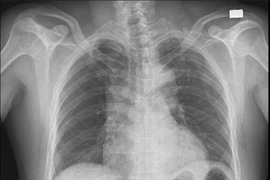

Bệnh viện Hùng Vương Gia Lai vừa cấp cứu và can thiệp động mạch vành thành công cho bệnh nhân bị nhồi máu cơ tim cấp biến chứng ngừng tim.

Đau ngực như dao đâm, người đàn ông bị lóc tách động mạch chủ nguy kịch

Lóc tách động mạch chủ xảy ra khi thành động mạch chủ – mạch máu lớn nhất của cơ thể bị rách và tách lớp.